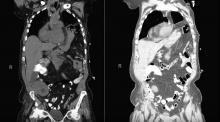

The authors present a video of a 65-year-old female with non-ischemic cardiomyopathy, who had a left ventricular assist device (LVAD) implanted as a bridge for transplantation. After the heart transplant, the patient developed profound shortness of breath and a diaphragmatic hernia was diagnosed. This video demonstrates the authors’ laparoscopic technique for performing a repair.